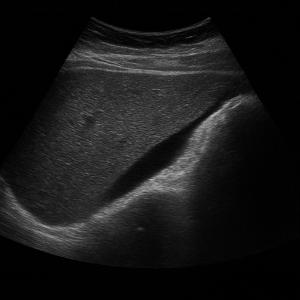

검사 시 체위와 초음파 탐촉자 사용

- 보통 검사는 엎드리지 않고, 천장을 보고 똑바로 누운 상태에서 시작해요. 팔은 머리 위로 올리기도 하고요 .

- 상황에 따라 옆으로 눕거나 반쯤 몸을 일으킨 자세, 숨을 깊이 쉬거나 참는 동작을 함께 할 수도 있어요. 이런 동작을 통해 간이나 담낭처럼 갈비뼈 아래 장기를 더 잘 볼 수 있도록 도와준다네요 .

- 검사할 때는 초음파 젤을 배에 바르고, 그 위에 탐촉자(프로브)를 밀착시켜서 움직이면서 장기 영상을 잡아요 .